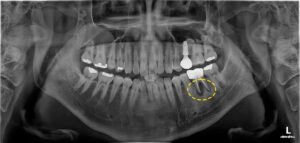

식립 전, 후 사진을 비교해 볼게요.

뼈이식이 된 부분은 발치 전과 달리

하얗게 보이는 모습을 볼 수 있어요.

약 3개월 정도 잇몸뼈와

임플란트가 유착되는 기간을

가지기로 하였고 추후 확인 결과,

임플란트와 잇몸뼈가 단단히 유착된

것으로 보여 보철물을 제작했어요.

마무리 후 사진이에요.